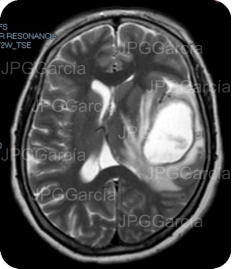

Resonancia magnética de cráneo en secuencias T1 y T2 que muestran una lesión ocupante de espacio de localización fronto temporal izquierda que ejerce efecto de masa aunado a edema perilesional